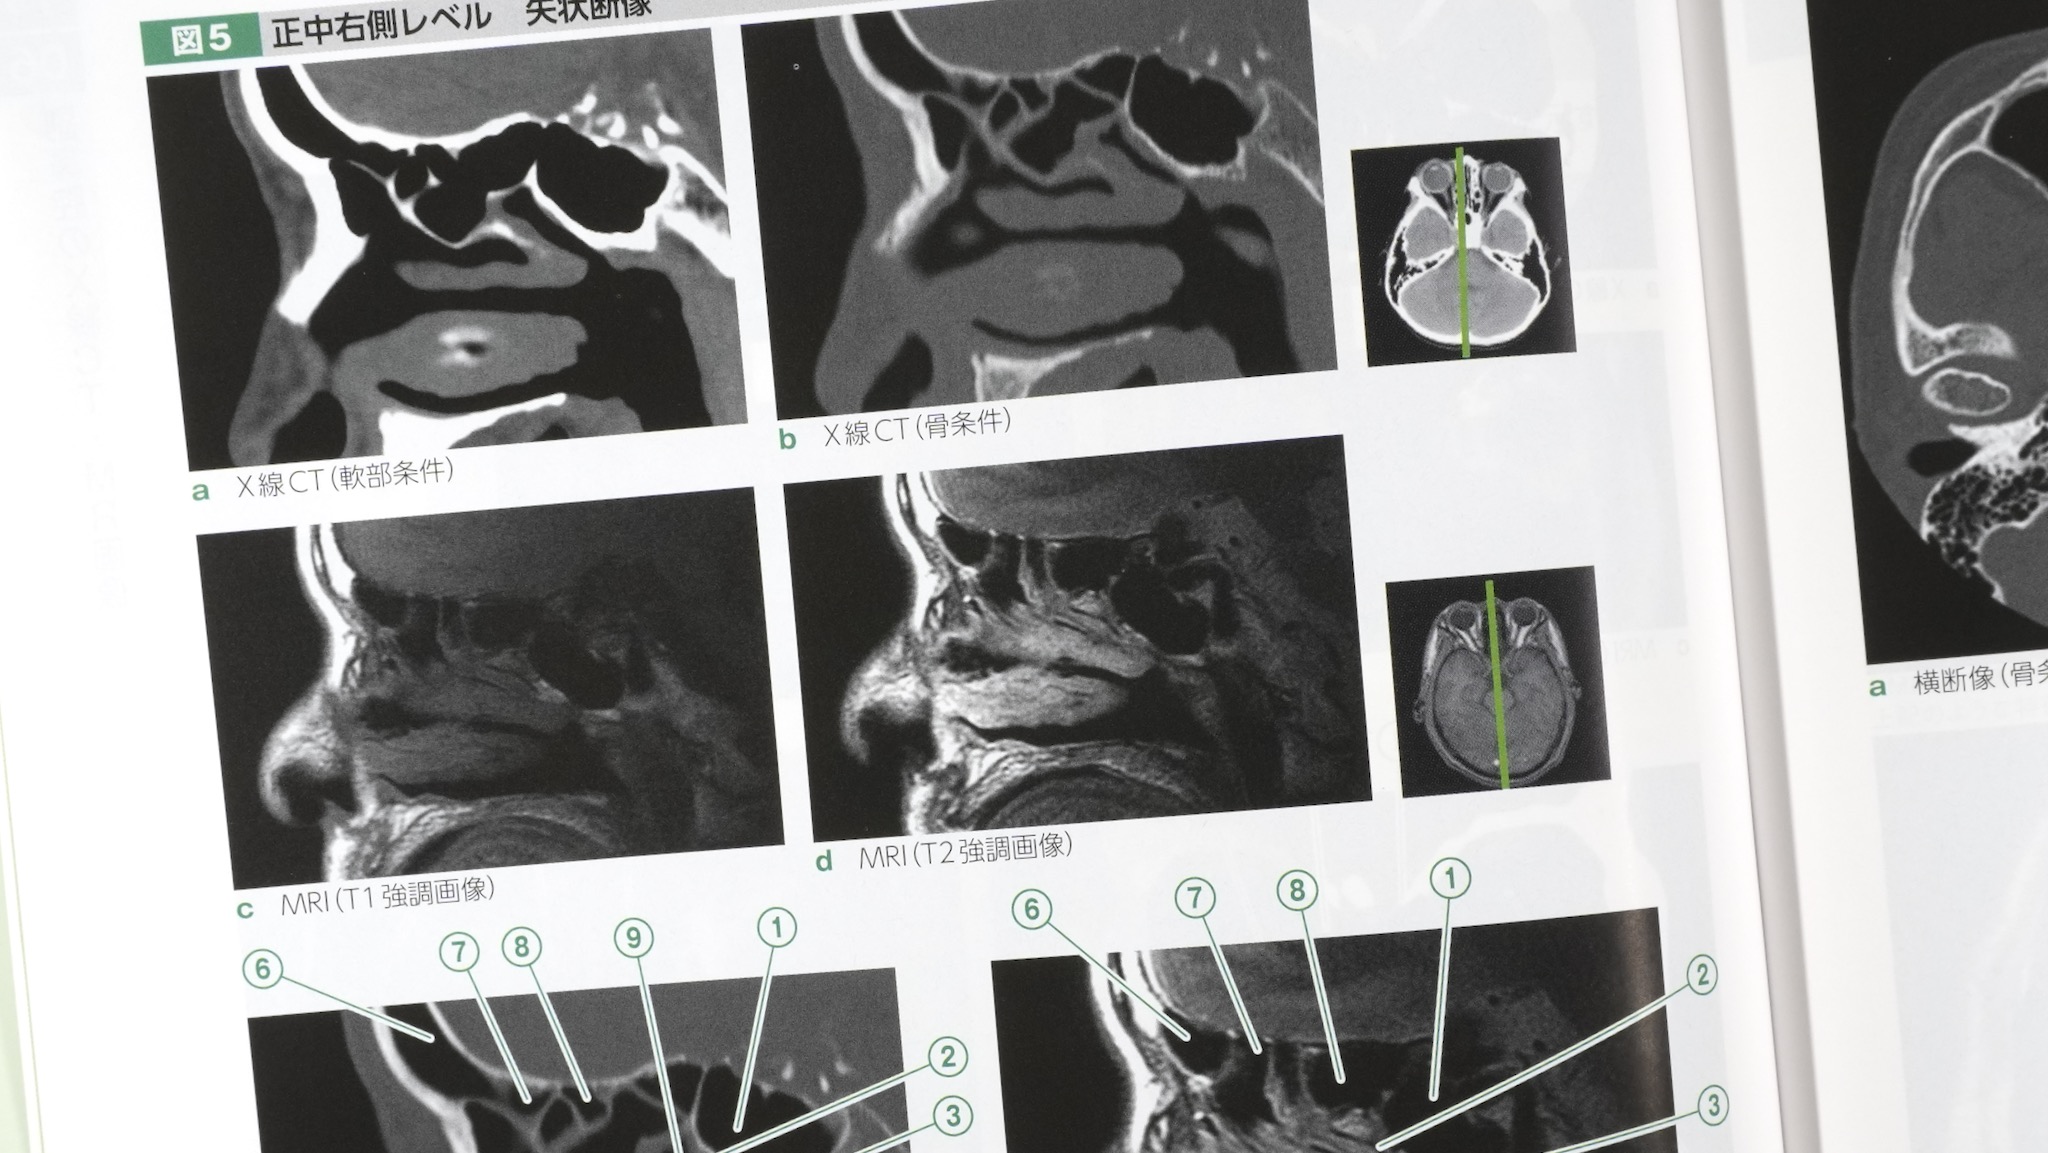

頭頚部のX線画像と部位の同定

頭部CTとMRIの対比と部位の同定